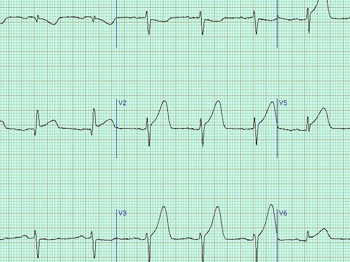

Блок ЭКГ. Современные УЗИ аппараты зачастую можно использовать вместе с другой медицинской техникой, например, с эндоскопами или при исследовании снимков срезов с КТ/МРТ. Не стала исключением и аппаратура ЭКГ. Просто подключите к данному УЗ сканеру элект

Тканевый доплер. Данная функция подарит вам возможность оценить сократительную способность миокарда. Как правило, она применяется вместе с импульсно-волновым доплером и помогает при проведении диагностики системных поражений сердца, кардомиопатии, ишемии

Анатомический М-режим. Благодаря этой функции вы получите возможность сделать до трех срезов одновременно в реальном времени, вращая курсор под произвольным углом без перемещения датчика. Таким образом, врач может увидеть графику движения структур сердца

Постоянно-волновой доплер. Благодаря данной функции вы сможете проводить количественную оценку кровотока в сосудах с высокоскоростными потоками, что активно используется в исследованиях эхокардиографии